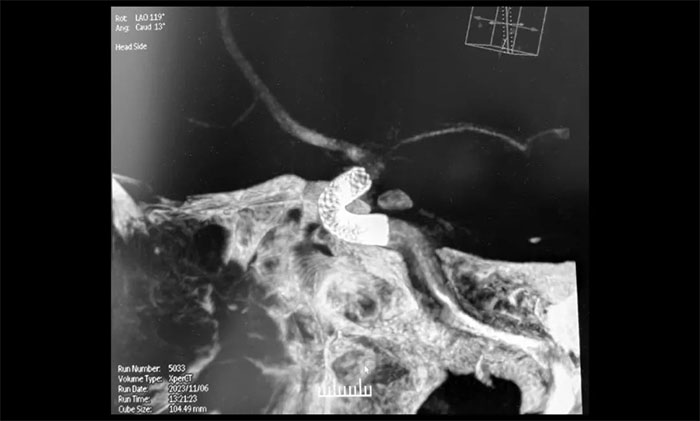

充分完善術(shù)前準(zhǔn)備后,11月6日上午,席剛明教授在麻醉科和介入手術(shù)室緊密配合下,歷時兩個小時順利進行了右頸內(nèi)動脈眼動脈段多發(fā)動脈瘤血流導(dǎo)向裝置(Pipeline)置入術(shù)。術(shù)中,微導(dǎo)管到位后緩慢釋放血流導(dǎo)向裝置到達術(shù)前預(yù)定位置,造影顯示血流導(dǎo)向裝置貼壁良好,完全封閉了動脈瘤瘤頸。多角度復(fù)查造影顯示,動脈瘤瘤腔內(nèi)有明顯造影劑滯留,載瘤動脈和分支血管血流正常。術(shù)后CT檢查,顱內(nèi)未見出血,手術(shù)順利完成,順利拆除埋在患者腦子里的“不定時炸彈”。術(shù)后,患者順利蘇醒,無新發(fā)神經(jīng)功能缺損。目前,患者已康復(fù)出院。

▲ 造影顯示血流導(dǎo)向裝置貼壁良好